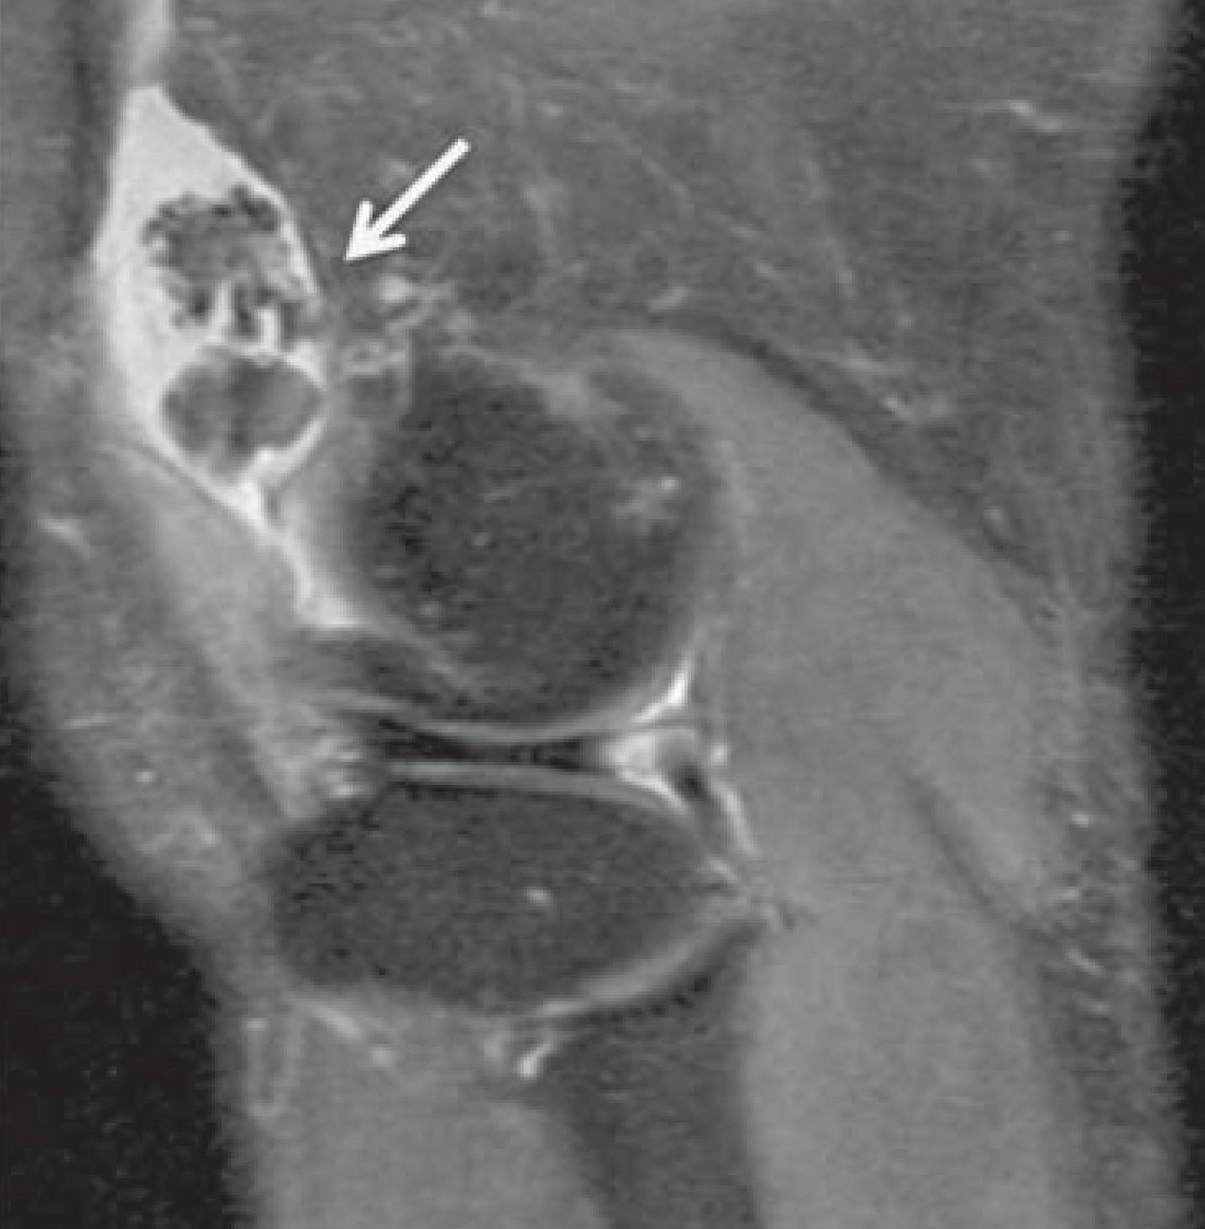

🧲 Resonancia magnética (RM)

Aporta valor cuando los cuerpos libres no están calcificados y para evaluar sinovitis, erosiones por presión, extensión extraarticular y afectación de tejidos blandos. El cartílago suele verse con señal baja/intermedia en T1 y alta en T2, con “vacíos de señal” si hay calcificación.